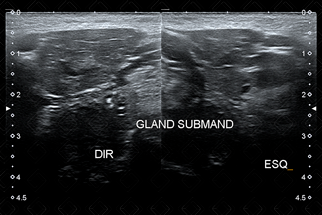

Texto alternativo para a imagem Figura 2. Em geral, depois segue-se com avaliação das glândulas submandibulares. Créditos: Dra. Elazir Mota - Rio de Janeiro/RJ